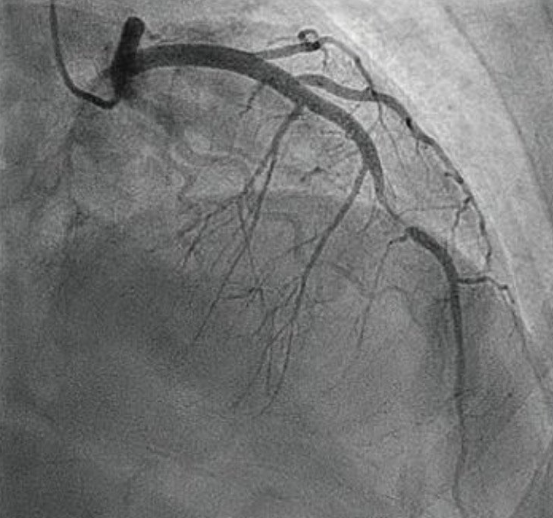

ACS的治疗常常通过冠状动脉造影明确诊断并进行微创介入手术然而造影并不能充分提供血管病变的病理生理学信息包括斑块性质与稳定性、血栓发生的几率与原因根据ACS的病理生理学分类与发病原因如何能够准确判读血管内膜的斑块性质结构特征等对治疗策略及急性心梗(AMI)的预防极为重要

冠脉造影显示狭窄病变             血管腔内影像显示极易破裂的斑块